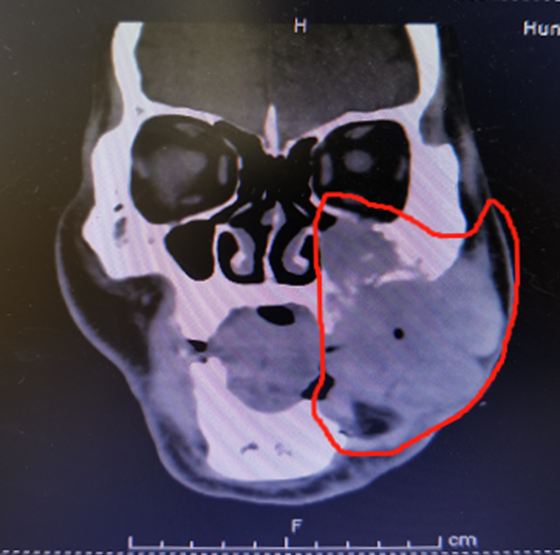

“后期恶性肿瘤的疯长速度肉眼可见,肿瘤很可能造成患者无法进食甚至呼吸,导致恶病质或窒息而危及生命,也很容易通过淋巴转移,甚至侵犯到眼球扩散至颅内。”湘雅常德医院口腔科主任伍栋详细介绍了郭先生的病情,“仅仅2个月,肿瘤从葡萄大小生长到鸡蛋大小,术前1周脸部皮肤开始持续性破溃加重流血水,肿瘤也从口腔内部穿过肌肉露在脸部,导致郭先生脸部外观严重畸形,肿瘤已经侵犯长满了郭先生的左半脸,向上侵犯到了眶底,向下到了颈部,甚至向颅底侵犯。”

修复如此大的缺损,在国内非常少见。郭先生的肿瘤切除后,一半脸将随肿瘤切除,同时还需要摘除左眼,留下的手术创面极大并且临近颅底,必须用身体其他部位的皮瓣通过吻合血管的游离移植立即对面部和口腔内进行双层修复,否则患者术后同样无法存活。